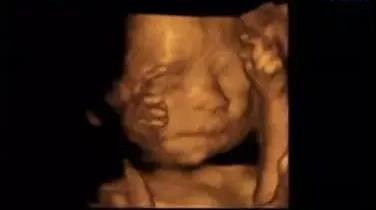

为了提前探寻这一“真相”

我们可以通过一个特别的仪式

在影像中让宝宝与爸爸妈妈提前相遇

感受宝宝与父母奇妙的连接

这一切,只需要选择四维彩超就可以啦

1、四维彩超最佳时间是孕24—26周。

2、做四维彩超检查前,孕妈们不要过于紧张,如果过于紧张会影响到腹中胎儿。

3、四维彩超检查不需要空腹。孕妈有饱腹感,宝宝会爱动一些,更易于做检查。